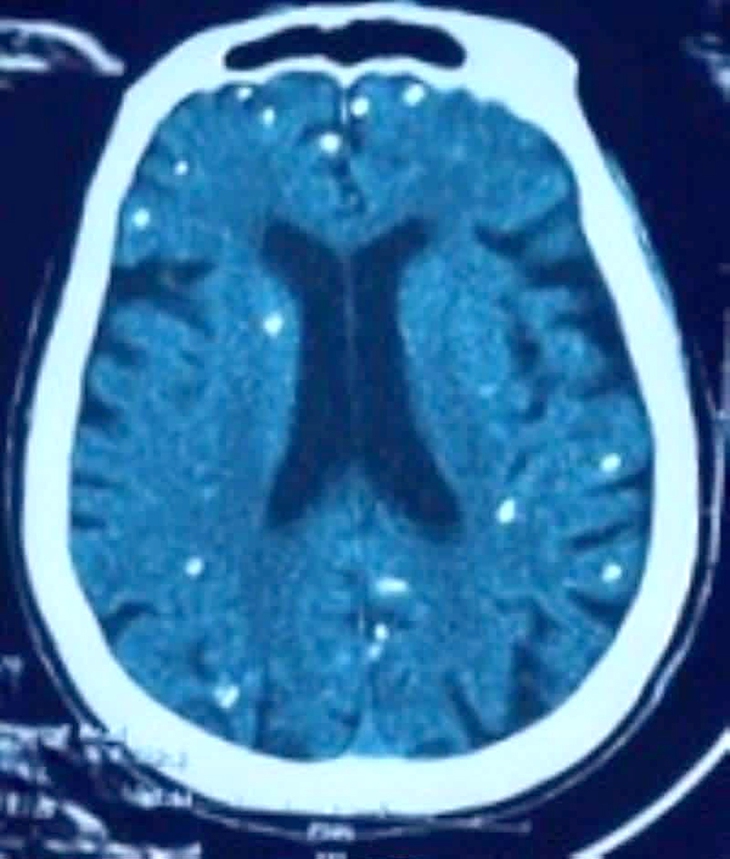

Người bệnh được chẩn đoán nhiễm ấu trùng sán dây lợn. Hình ảnh cắt lớp vi tính sọ não và X-quang ngực cho thấy rất nhiều nốt cản quang trong nhu mô não và dưới da vùng ngực - bụng.

Nhiều nốt cản quang trong nhu mô não của người bệnh - Ảnh: BVCC